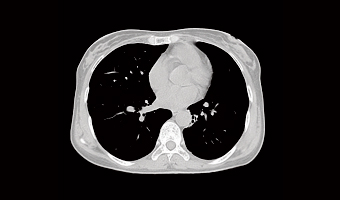

Application Images